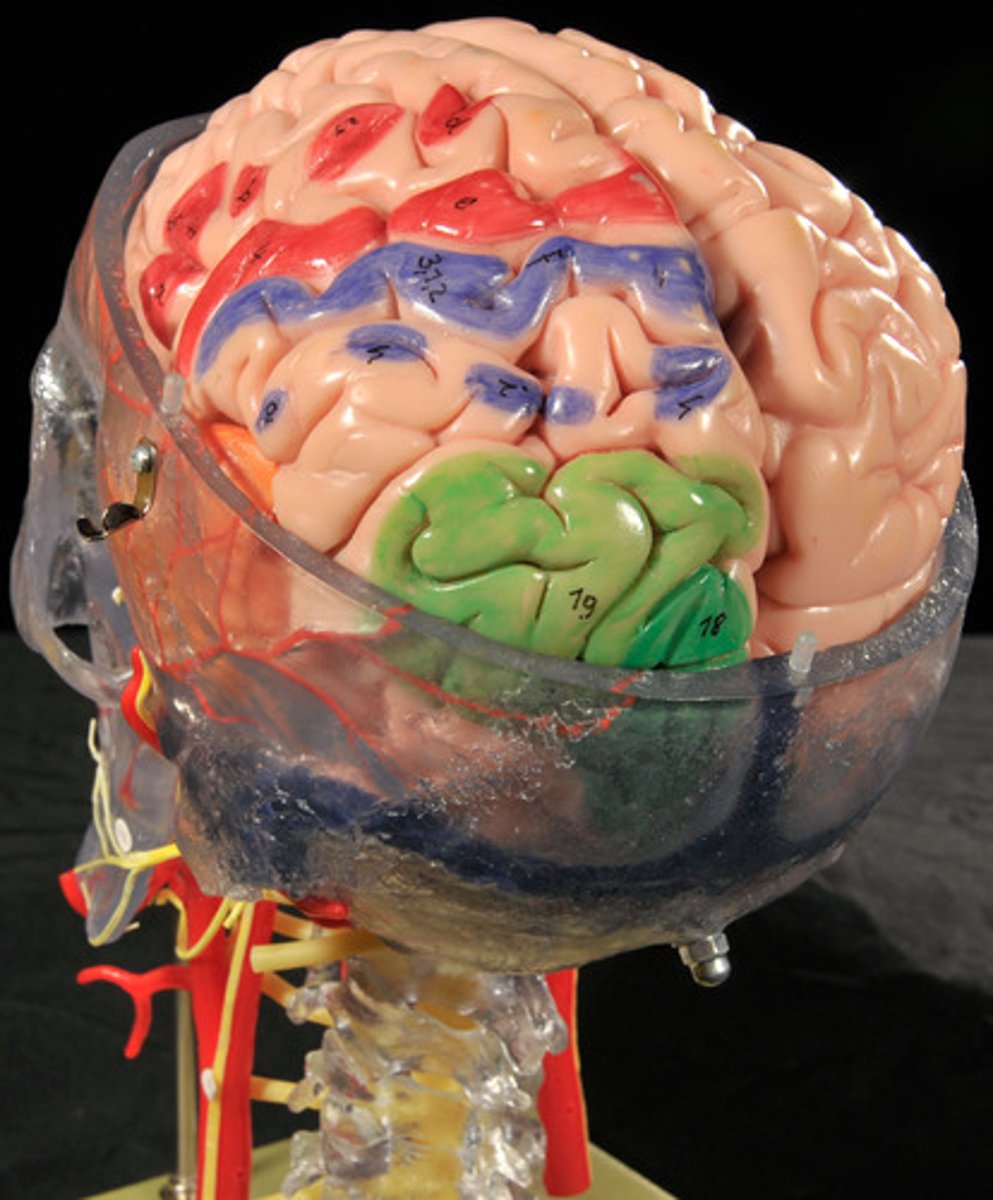

Cerebral Hemispheres (Cerebrum)

Paired (left and right) superior parts of the brain,

Largest Portion of the Brain,

The surface is made of elevated ridges called gyri and shallow grooves called sulci

Cerebrum: Sulci and Gyri

Central Sulcus,

Precentral gyrus,

Postcentral gyrus

Surface lobes of the cerebrum

Frontal Lobe,

Temporal Lobe,

Parietal Lobe,

Occipital Lobe

Frontal Lobe

Primary (somatic) motor cortex

Temporal Lobe

Olfactory and Auditory input

Parietal Lobe

Reception and evaluation (integration) of sensory information except for smell, hearing, and vision

Occipital Lobe

Vision and integration of visual input

Frontal lobe: motor cortex

1) Controls precise or skilled voluntary movements of our skeletal muscles

2) Also learned motor skills (repititious or patterned nature) like playing an instrument or typing

3) Is contralateral: left primary motor cortex controls muscles on right side of body & vice versa